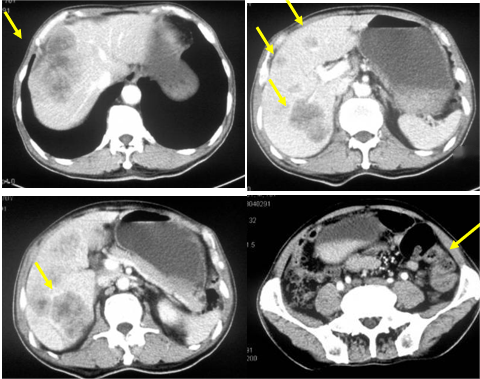

CT提示:降结肠-乙状结肠交界不均匀增厚并肠腔狭窄,考虑恶性病变,肝内多发结节、肿块,考虑转移瘤(图2);肠镜提示:乙状结肠肿物,病理:中分化腺癌。